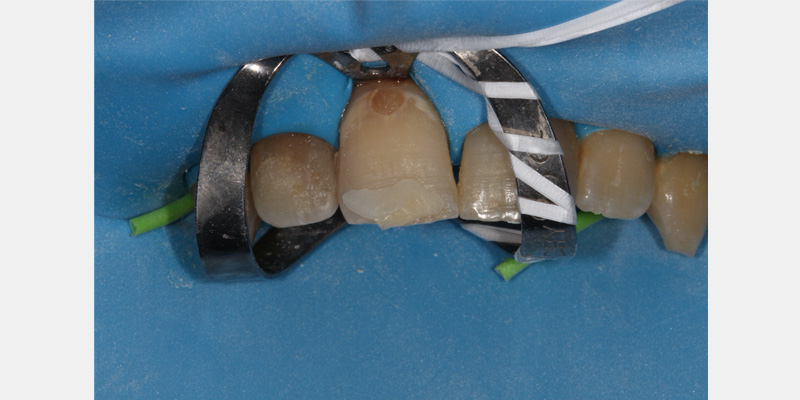

Clamps can fracture over time due to wear and tear. This most commonly occurs at the clamp’s bow. To avoid a fractured clamp becoming an aspiration risk, it’s recommended to ligate floss through one hole, around the bow, and through the opposing hole in the clamp.

Another common issue is the leakage of oral fluids through the dam. One way to mitigate this is by selecting the proper-sized holes for the teeth being isolated.

Invariably, leakage may still occur. After the rubber dam is placed, a caulking material can seal any areas that may still have leakage. Various products are available on the market; however, unbonded composite can also be placed and light-cured to act as a caulking agent.

Floss should be used to push the dam through the contact areas of the teeth. After passing through the contact point, the floss can be used to help invert the dam by gently working the floss in to the gingival sulcus. Pulling the floss out buccally, rather than back through the contact point, can help minimize the risk of having the dam dislodge from the tooth.

In some instances, light or open contacts may exist between adjacent teeth, which can present a challenge for securing the dam. Fabricating a floss ligature using a square knot can help secure the dam around the tooth. If this does not work, a thicker material (such as a Wedjet) can be used to hold the dam in place. Alternatively, a corner of the dam can be cut off and used interproximally to secure the dam.